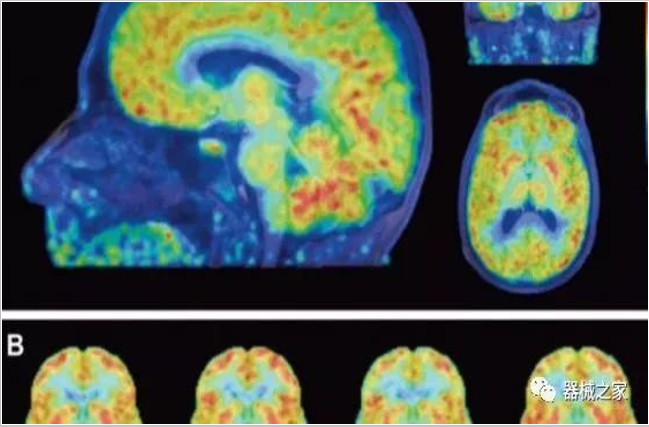

PET掃描顯示成年女性大腦比男性年輕三歲!